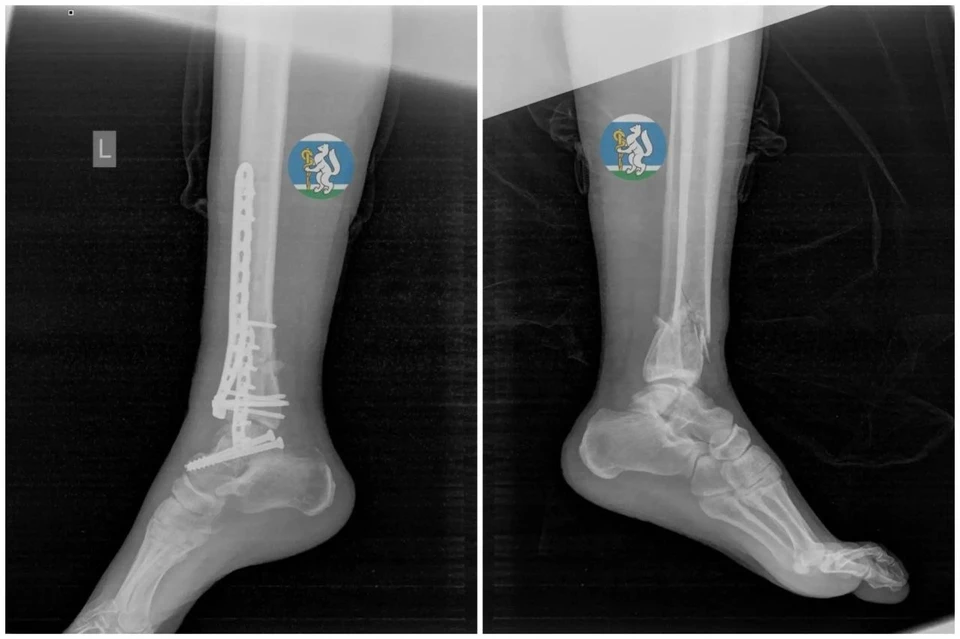

У женщины диагностировали черепно-мозговую травму, повреждение шейных позвонков, переломы костей таза, травмы грудной клетки и легких, а также оскольчатые переломы левой ноги. Многие пострадавшие с такими травмами погибают до приезда скорой помощи.

После операции женщина находилась на ИВЛ до полной стабилизации. Через полторы недели ее перевели в отделение травматологии, а еще через две недели врачи удалили аппараты внешней фиксации.